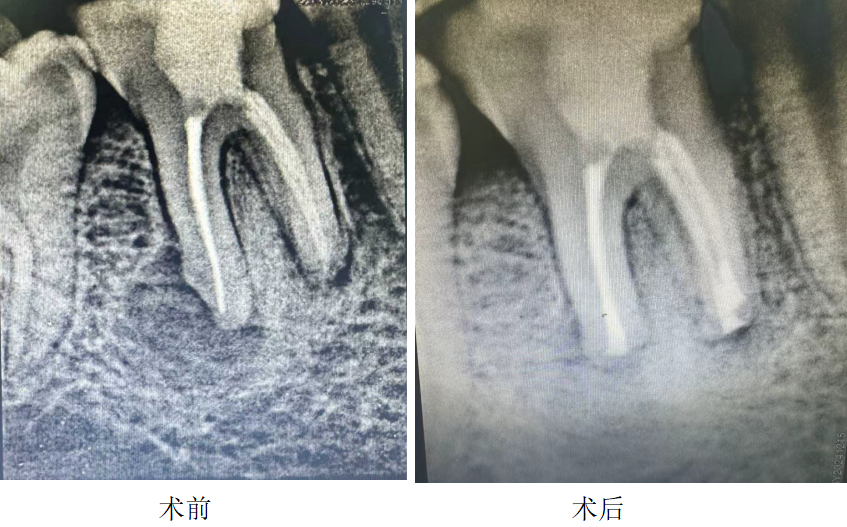

精准再植 护齿原牙|显微镜再植术为疑难患牙“留生机”

显微镜下意向性牙再植术是一项针对疑难患牙的保牙新技术,依托高倍率牙科显微镜的精准引导,针对常规根管治疗、根尖手术无法治愈的病变牙齿,采用微创方式将患牙完整拔除,在体外对病灶进行彻底清理、对牙齿缺损部位进行精准修复后,再将患牙重新植入原有牙槽窝,助力天然牙恢复正常生理功能,是目前口腔诊疗领域兼具精准性与微创性的先进技术之一。

与传统治疗方式相比,这项技术的临床优势十分显著:传统拔牙后种植治疗,不仅可能损伤邻牙及更多牙槽骨,而且治疗周期较长;而显微镜下意向性牙再植术可最大程度保留天然牙的生理感知功能,显著提升患者咀嚼舒适度,结合个性化固定方案,治疗过程创伤小、术后反应轻,能帮助患者更快恢复,有效减少诊疗过程中的不适感。

“以前碰到这类疑难患牙,临床上大多只能采取拔牙处理,患者不仅要承受缺牙带来的生活不便,后续种植治疗还需承担相应费用。”林晶介绍,目前科室已搭建起全周期天然牙保护体系,可根据患者患牙类型、病变严重程度及口腔整体条件,定制“显微镜再植+根管治疗”等个性化诊疗方案,实现从病变控制、牙齿修复到长期养护的全流程覆盖。从术后随访情况来看,患者患牙稳固率良好,对咀嚼功能恢复的满意度也较高。